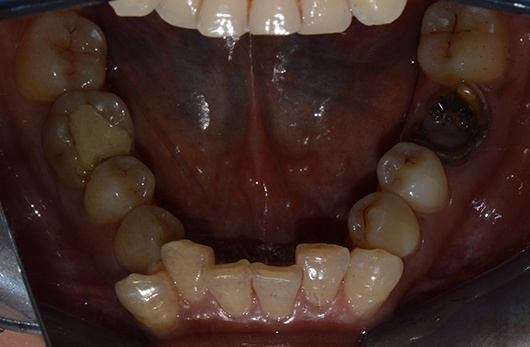

首先第一个是因为六龄齿已经蛀到只剩残根,拔除后我们打算把第二磨牙和智齿前移,关闭拔牙间隙,使智齿变废为宝。

第二个case是已经开始矫正了一年半,当初智齿还是阻生的,但角度很好,经过矫正,今天黏上颊面管,纳入矫治,已经变废为宝了,六龄齿的间隙快要被完全关闭了。这样做当然比拔除两个第一前磨牙排齐所费周章,但能多保留两个天然健康的牙齿,也是一辈子收益的。

第三个case就是不听劝说,没有及早拔除智齿,以至于智齿阻生越来越严重,增加手术难度,当然病人自己术后也会更难受。

智齿的存在我们看X光片就可以预计它能否顺利萌出,如果阻生,应该尽早拔除。

智齿的存在也是后牙段拥挤的始作俑者,我们眼睛往往只着重于前牙拥挤,没有看到后牙如果有倾斜、扭转等等也是拥挤的表现。